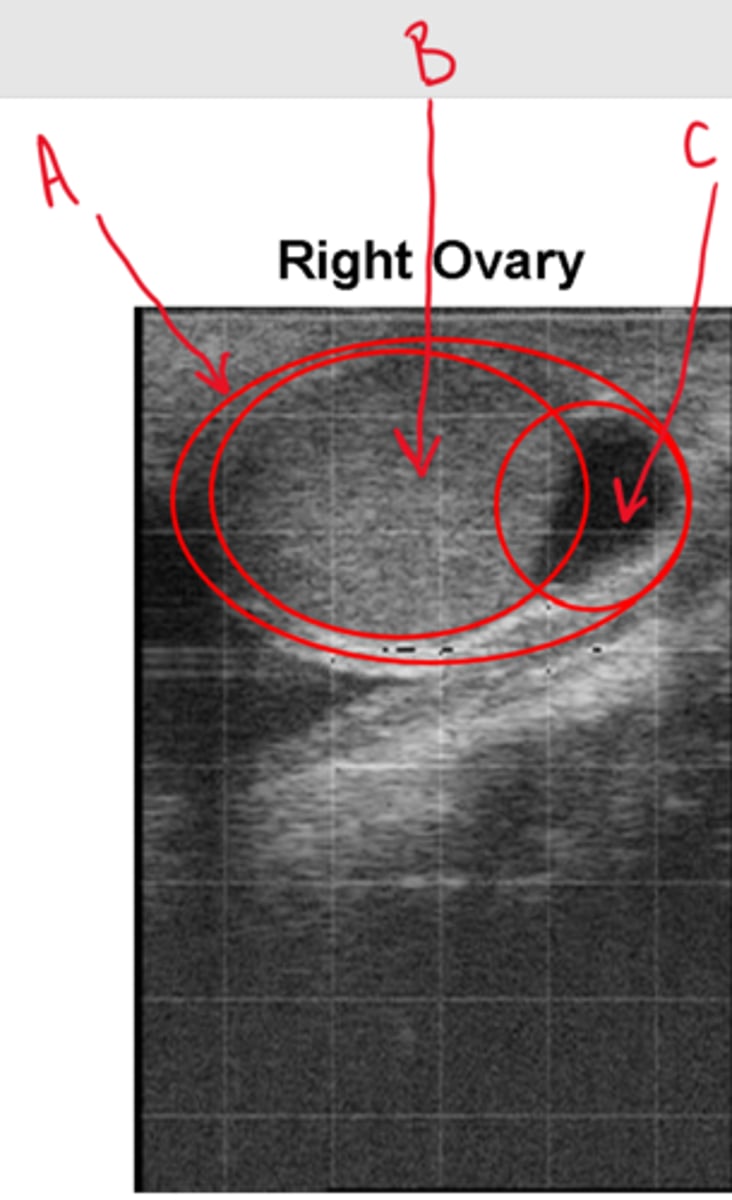

<p>Label this ultrasound of the right ovary</p>

Label this ultrasound of the right ovary

A = Ovary

B = CL

C = Follicle